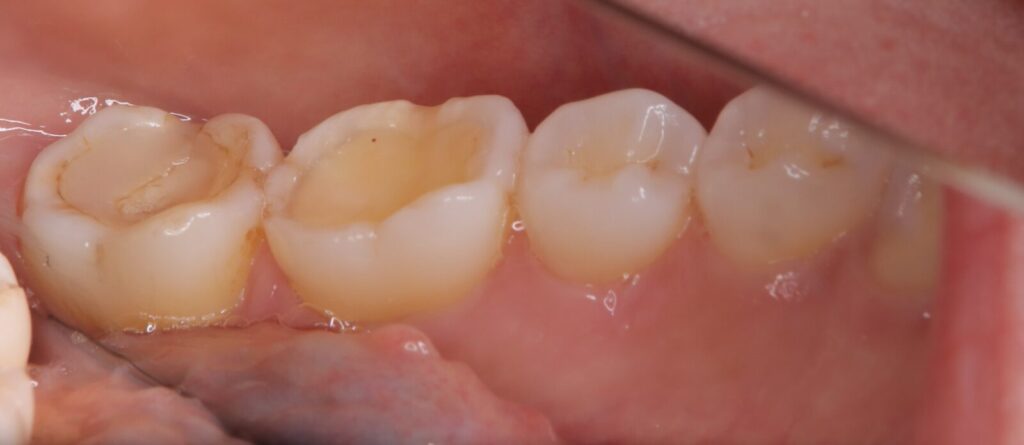

写真の2本の大きな奥歯(大臼歯)にご注目ください。

本来、奥歯には噛み合わせるための複雑な凸凹がありますが、

このケースでは平らにすり減ってしまっています。

原因:

過去の修復物における噛み合わせ調整の不備などにより、

特定の歯に過度な力がかかり続けた結果と考えられます。

リスク:

すり減りによって歯の内部にある「象牙質」が露出しています。

象牙質は外側のエナメル質よりも柔らかいため、

虫歯の進行が非常に早く、歯を失うリスクが急激に高まります。

一番左の奥歯(7番)の噛み合わせの面には、

白い詰め物が「つぎはぎ」のように何度も重ねられた形跡がありました。

問題点:

不適切なレジン修復を繰り返すと、

素材同士の間に微細な隙間(つなぎ目)が生じます。

結果:

この隙間はバクテリアの格好の棲家となり、内部で繁殖が進みます。

見た目が白くても、その裏側で

「二次カリエス(再発した虫歯)」

が進行していくという、非常に恐ろしい状態です。

さらに深刻なのは、歯の側面に見られる縦方向の

「破折線(ヒビ)」です。

細菌の侵入:

ヒビの内部にはすでにバクテリアが侵入し、黒く変色していました。

歯周組織への影響:

この部分の歯肉は赤く腫れ、歯周ポケットの深さは「5mm」に達していました。

これは中等度以上の歯周病が進行しているサインであり、

歯を支える骨が溶け始めている可能性を示唆しています。